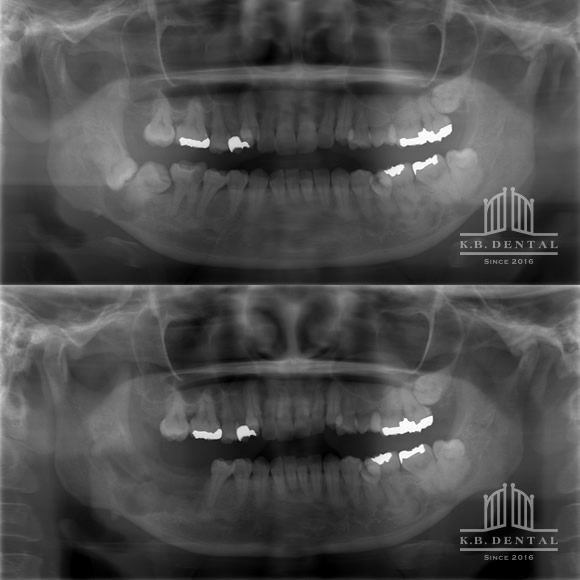

術後2年経過の最も典型的なエナメル上皮種です。再発率が非常に高いので最低でも5年以上の経過観察が必要となります。今回は摘出術と一部健常域まで辺縁切除(骨を削る)を行いました。

1枚目(パノラマ)上:術前 下:術後 摘出部分に新生骨を認めます。